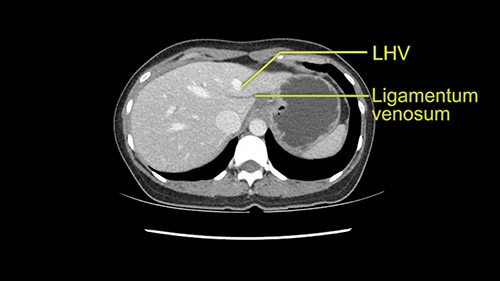

Anatomically, to plan for a left lateral segmentectomy, it’s relatively easy as far as liver surgery goes. I know that I'm going to be looking for the left hepatic vein which will be divided at some point either towards the end at the back near the vena cava or through the middle of the left lateral segment.

I generally take the ligamentum venosum to get access to the left hepatic vein. In this case, not necessarily but we certainly need to think about it.

The transection line will be a little more obvious. There’s a little patch of focal fat here in Segment 4b but we’ll describe the transection line probably through the mid portion of Segments 4a and b up to the top. Up at the top, the left hepatic vein can be taken. There’s a Segment 3 vein or the so-called falciform vein it’ll be rudimentary so I think we’ll be able to get around the left hepatic vein and leave the middle [hepatic] vein intact because it’s free of tumor.

Her vein, it looks like a combined middle and left hepatic vein, it may be encircled during the case as a whole common trunk but most probably it will not be a big deal because if it is okay to go with the left lateral resection, the vein or the left hepatic vein can be catched during the intraparenchymal dissection and can be controlled in that side.

The next step would obviously be the left hepatic vein mobilization. Once you lift the left lateral segment up, and you mobilize from the caudate lobe, you’ll find that you need to identify [Arantius’ canal] and ligate [Arantius’ canal], then only the left hepatic vein comes into view at the apex of the caudate lobe. In this particular case, because the hepatic venous plane is intact and its pretty free, it’s quite easy to ligate the left hepatic vein and staple it off. That would complete the devascularization of the tumor.

The other option of course is to do an anatomical left hepatectomy. In that case, I will start mobilizing of course the left lobe and try to find the ligamentum venosum, take it down and go around the left hepatic vein. I think, importantly in these cases and in this case, as you can see in the venous phase, that’s clearly a moment to stop. Because the left hepatic vein is pretty close to the middle hepatic vein as sometimes it is so you may need to dissect a little bit the parenchyma on top of the left hepatic vein to be able to go around the left hepatic vein safely.